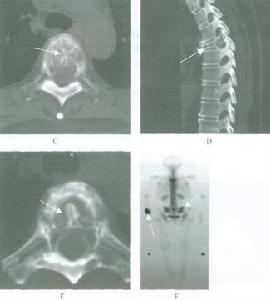

普通X線檢查包括頸椎常規片和斷層片。創傷性樞椎前滑脫的診斷主要依靠側位片。側位片可清楚地顯示骨折線及移位的成角的情況。據此可作出骨折類型的影像學診斷。在醫師陪同保護指導下,謹慎地作頸椎伸、屈位拍片,可進一步提供骨折穩定情況的信息。有時尚需作斷層檢查才能清楚顯示骨折線。X線的典型表現是雙側樞椎椎弓根骨折,骨折線呈垂直或斜形,樞椎椎體可有不同程度的移位和成角畸形。另需注意寰椎、下頸椎有無伴隨骨折,對嬰幼兒還需注意樞椎椎弓根先天性缺損或軟骨連結的可能。

CT檢查可清楚顯示骨折線,移位情況及與椎管的關係。CT三維重建有肋於對骨折形態的全面了解。MRI檢查可了解脊髓及周圍軟組織的情況對整個損傷可有全面的評估,並為手術入路的選擇提供依據